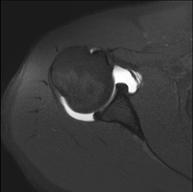

- RM d'Espatlla

Exploració per a l'estudi de lesions en els tendons, els músculs i les articulacions. La seva principal utilitat resideix en diagnosticar les lesions dels tendons del braçal rotatori. Té una durada aproximada de 20 minuts. No utilitza radiació ionitzant. - RM de Braç

Exploració per a l'estudi de lesions en tendons, músculs i petites articulacions. Permet valorar amb eficàcia les lesions al cartílag. També és de molta utilitat per completar l'exploració ecogràfica prèvia. No empra radiació ionitzant. Té una durada aproximada de 20 minuts. - Artro-RM d'Espatlla

Exploració per a l'estudi de les lesions en petites estructures anatòmiques de l'articulació que solen lesionar-se en pacients que pateixen luxació o inestabilitat crònica. L'estudi ve precedit per una injecció de contrast a l'interior de l'articulació, realitzada sota control de raigs X. La durada total dels dos procediments és de 50 minuts. - Artro-RM de Canell